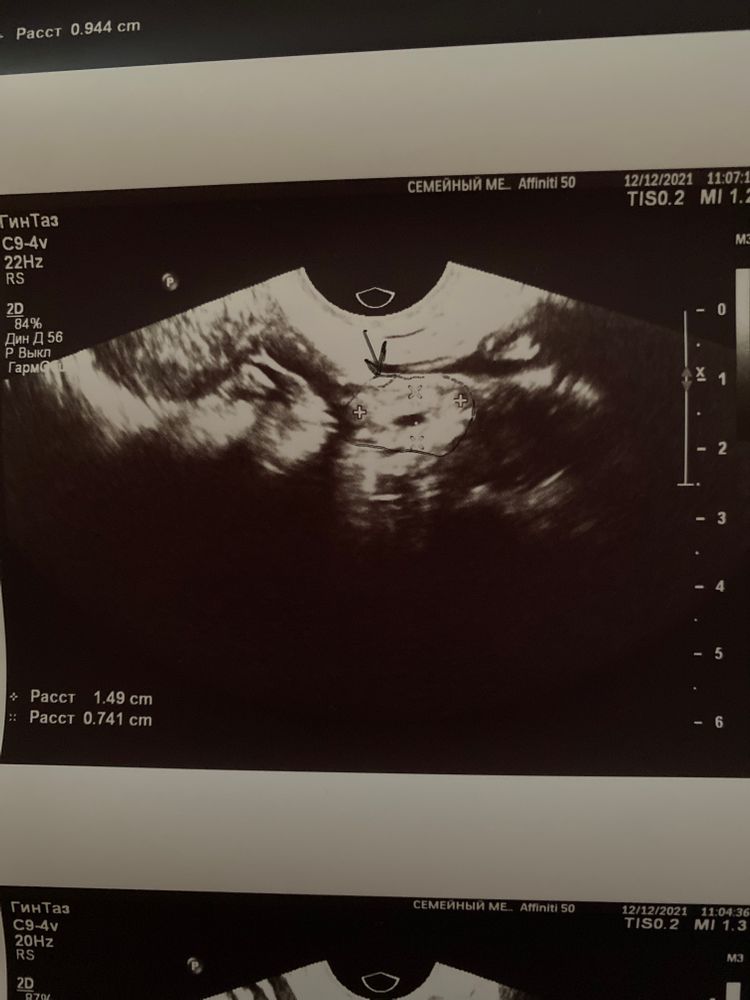

Двурогая матка !!!

Девочки ,добрый день 💐💐💐Сегодня была на УЗИ ,сказала врачу про мазню и про задержку ,она посмотрела и сказала,что у меня двурогая матка и скорее всего подозрение с левой стороны внематочная ,ну не может быть ,я помню точно ,что с левой стороны мне удаляли трубу ,жду теперь анализы ХГЧ ,я ей сказала ,что признаков у меня нет никаких ,как было с первой внематочной ,УЗИ сказала ,что всякое может быть ((((Может всё таки беременность,раз двурогая матка ?)))У кого как проходила беременность при двурогой матки ?

KUZOVOk, про ВБ сказали на УЗИ )))Но я понимаю ,что там нет трубы ,какая беременность в трубе )))Поэтому она написала ,что подозрение на трубную беременность слева ((((а ХГЧ у меня был 156 ,а потом 154 (((Он слишком медленно падает ,это вот интересно (((

anabeta, а у вас были какие-либо подозрения на беременность?У меня просто мажет и температура держится уже 2 недели 37 (((и тест со слабой полоской ,ХГЧ сдавала 2 раза ,первое 156 ,второе 154 .Прошло 3 дня и сегодня повторно сдала ХГЧ )))